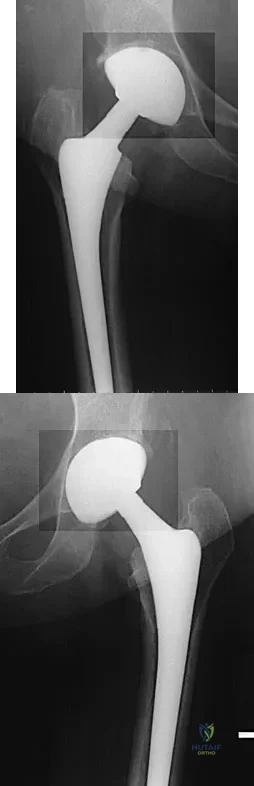

A 68-year-old woman underwent a successful total right hip arthroplasty with a metal-on-metal articulation and cementless porous-coated components. Three months later, she underwent identical surgery on the left hip. Three months after surgery on the left hip, she reports groin pain on ambulation. Examination reveals significant groin discomfort with passive hip motion, particularly at the extremes of motion. Radiographs are shown in Figures 21a and 21b. Laboratory studies show an erythrocyte sedimentation rate of 35 mm/h and a C-reactive protein of 0.9. Aspiration yields scant growth of Staphylococcus epidermidis in the broth only, with no evidence of loosening on arthrography. A second aspiration yields scant growth of Staphylococcus epidermidis in the broth only. What is the most likely cause of the patient's pain?